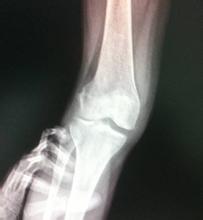

导读: 增生性骨关节病是指由于关节退行性变,以致关节软骨被破坏而引起的慢性关节病。又称退化性关节炎、骨关节炎及肥大性关节炎等。

导读: 随着年龄的增长,体质逐渐下降,骨骼逐渐退变,生理功能逐渐降低甚至丧失,因此有不少老年人容易患有骨性关节炎。而关节退变不仅包括年老所导致,日常的行为不当也可能加重关节退变。下面我们就一起来看看老年性骨关